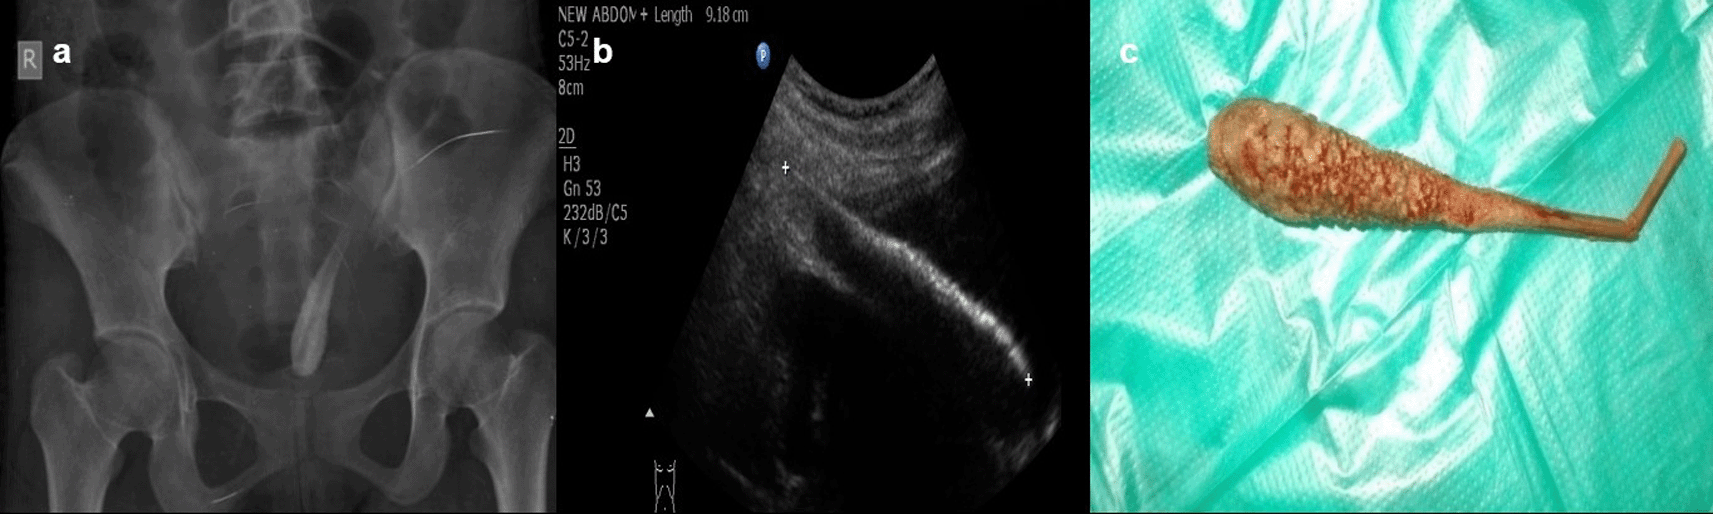

Case 6: A 17-year-old woman came for an ultrasound examination in emergency hours with complaints of severe pain in her lower abdomen. Radiograph Pelvis anteroposterior (AP) view revealed long radio-opacity in the bladder with a radiolucent center that did not look like a calculus, but a foreign body. USG revealed a linear hyperechoic foreign body that penetrated the anterior wall of the bladder. The patient had a history that she had conceived three years ago and had tried abortion by a quack in her village. The patient was operated on and a shaggy piece of a long wooden stick with cotton wrapped around it was found.

The rectum, vagina, urethra, ear, and nose are common places for foreign items to be inserted. These are especially common in children (Figure 5a,b) but can also be seen in adults. The deposition of mineral salts is especially likely to occur in foreign bladder substances, resulting in the formation of bladder calculi (Figure 6a,c). In fact, when a child or young adult develops a bladder calculus, the presence of an embedded foreign body should be suspected.10

USG revealed a linear hyperechoic foreign body that penetrated the anterior wall of the bladder (b). The removed foreign body was a long wooden stick with cotton wrapped around it (c).